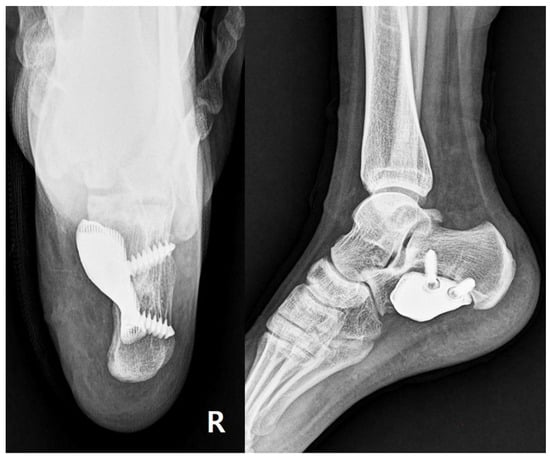

Postoperative radiographs confirmed stable prosthesis placement and proper alignment (Figure 8). The pathological findings were consistent with low-grade chondrosarcoma (Grade I).

Figure 8. Postoperative imaging. Postoperative radiographs of the ankle in anteroposterior and lateral views showing stable fixation with a locking plate with proper prosthesis placement.